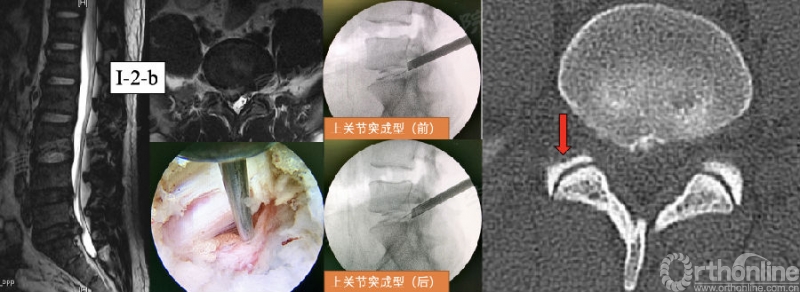

第25例:男,32岁,L5/S1 LDH(I-2-b)。

李利军教授将关节突成型分为5级:0级:不成型。1级:软组织成型(适用于:L1/2/3/4,椎间孔较大,3或4区突出)。2级:少许骨质成型。3级:上关节突上1/2成型(适用于:L4/5/S1,椎间孔较小,1或2区突出)。4级:上关节突大部分、椎弓根和部分下关节突成型(适用于:椎管狭窄,或突出伴钙化,需要操作空间大)。

建议对L4/5和L5/S1节段I或II区突出的病例进行1-3级成型,这将有利于充分减压,同时不破坏关节突稳定结构。对于椎管狭窄症患者可尝试进行4级成型,有利于黄韧带减压。常用的成型方法有:1、利用工作通道直接成型;2、镜下骨刀成型;3、环锯成型;4、镜外环锯成型。